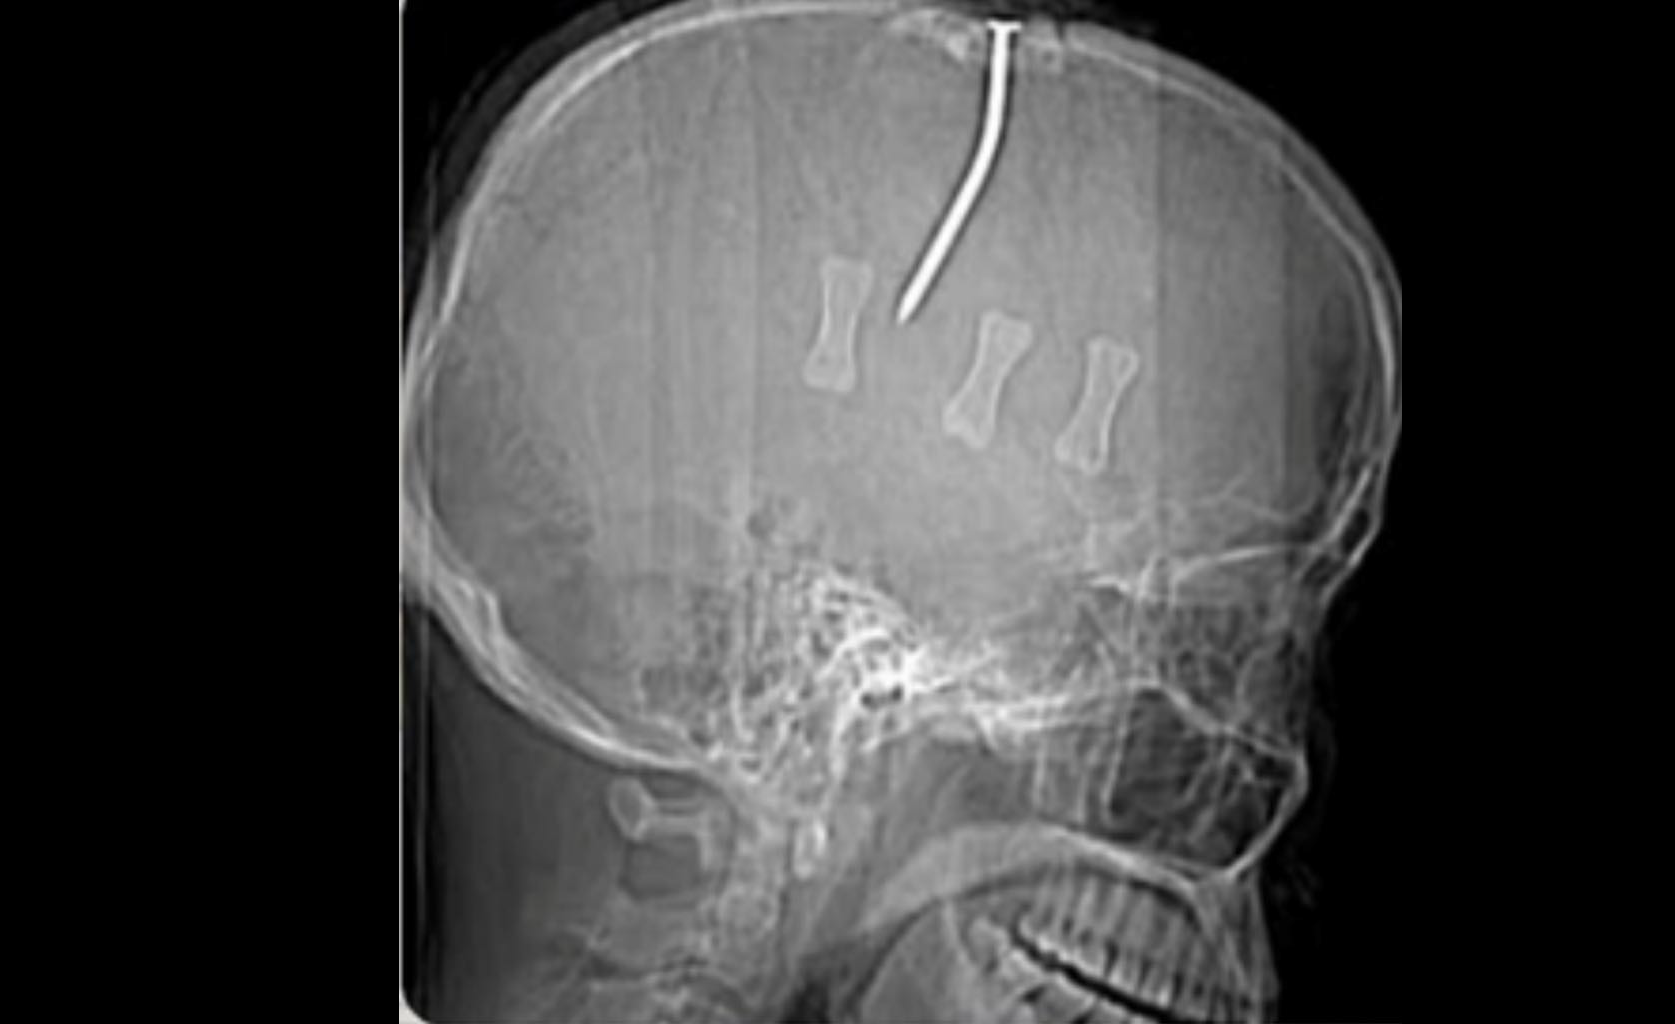

Ngay sau khi tiếp nhận bệnh nhân, các bác sĩ Bệnh viện hữu nghị Việt Tiệp đã tiến hành chụp cắt lớp vi tính, phát hiện hình ảnh dị vật kim khí dạng đinh đâm xuyên qua xương đỉnh và nhu mô não thùy trán trái và não thất bên trái gây vỡ xương đỉnh, gây xuất huyết não rải rác vùng đỉnh trái, nhiều bóng khí nội sọ, tràn máu não thất.

Qua thăm khám ban đầu, các bác sĩ nhận định đây là một ca bệnh cực kỳ nguy hiểm, mang tính chất phức tạp do chiếc đinh sắt xuyên qua hộp sọ, đi sát các cấu trúc thần kinh quan trọng và mạch máu lớn.